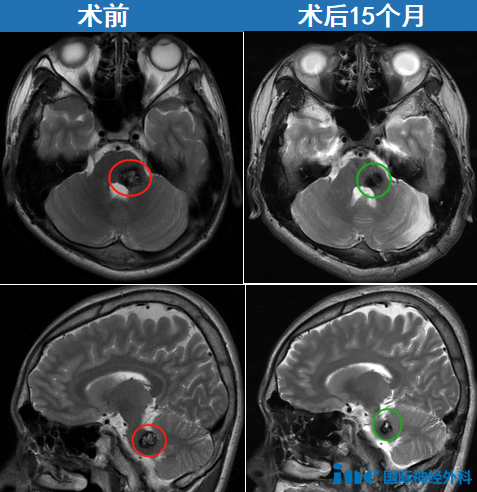

▼病灶位于桥脑左侧,并且与桥臂的交界处,病灶大,位置深。

小波术后15个月随访肢体灵活,未见面瘫及展神经功能障碍: